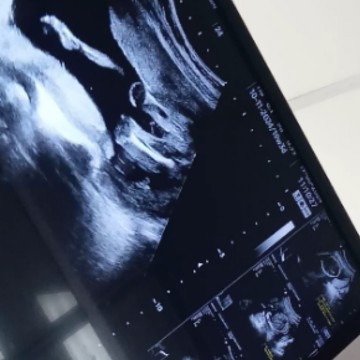

แม่ๆดูออกมั้ยคะว่าเพศอะไร

หมอบอกได้ผู้ชาย80% เพราะน้องหนีบขาแต่ไม่เห็บกีบ ตอนนี้ได้20wค่ะ

น่าจะหญิงค่ะ